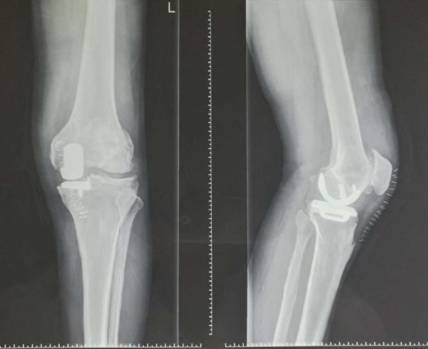

术前术后对比

全膝关节翻修术

全髋关节翻修术

全膝表面置换术治疗重度骨关节病

优点:疗效可靠,膝关节病的最终解决方案。